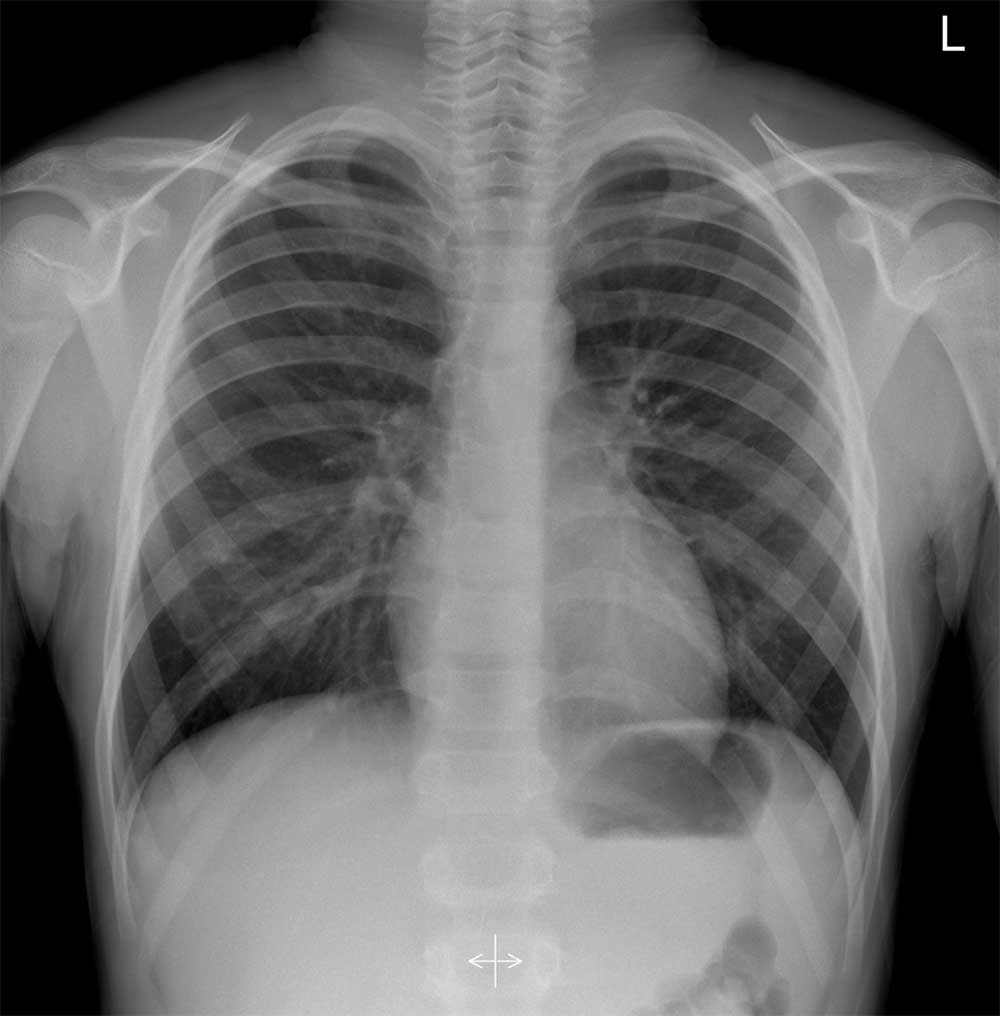

1. X-ray

X-ray tube (광원)에서 X-ray를 피사체에 쏘면 X-ray의 에너지가 높기 때문에 피사체를 통과하게 된다. 통과된 신호를 Detector에서 받아들인다. X-ray가 몸에 있는 tissue(공기, 뼈, 근육 등)를 통과하면 tissue의 intensity(강도)에 따라 통과된 에너지가 달라진다. Detector는 피사체를 통과해서 받은 X-ray를 전기 신호로 바꾸어 영상을 만들어낸다.

X-ray 이미지 : www.radiologycafe.com/radiology-trainees/frcr-physics-notes/x-ray-imaging